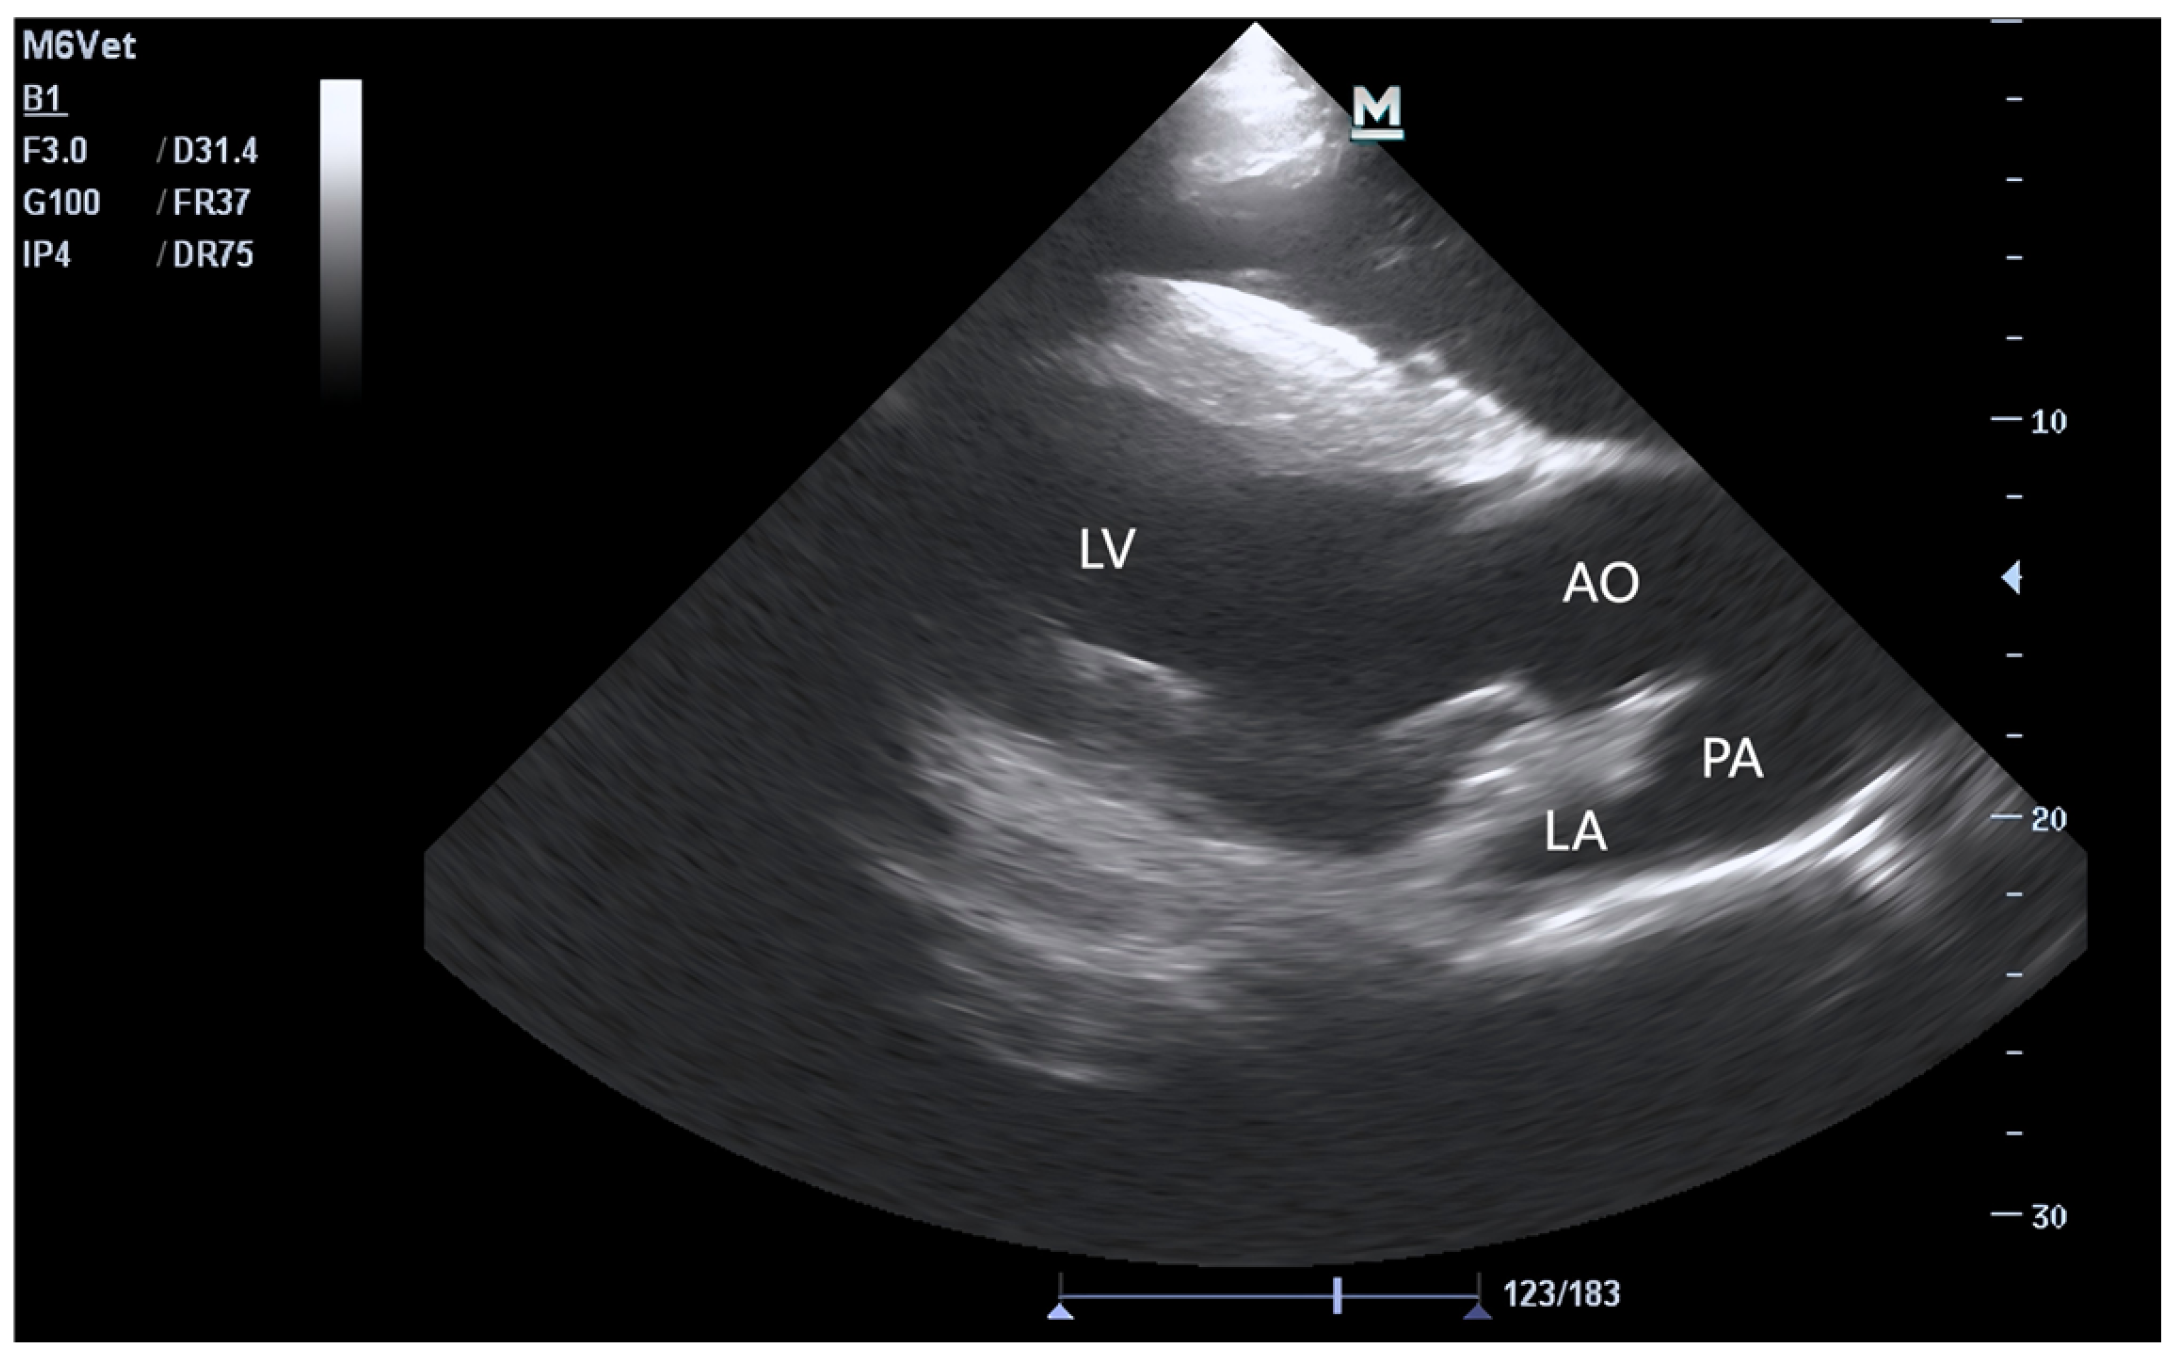

2.3. Echocardiography and Blood Sample Collection

3.1. Echocardiographic Parameters of Horses